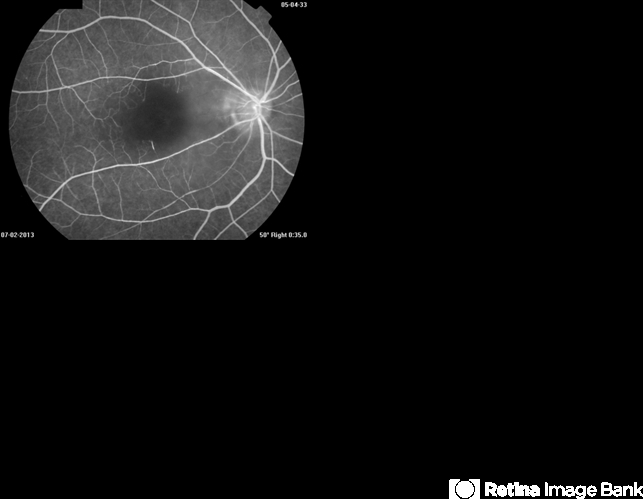

- Cilioretinal Artery Occlusion

- Avris Siahaan, Klinik Mata Nusantara, Jakarta, Indonesia

Fundus camera

Topcon TRC 50DX Type IA - Description

- Early FA of an 46-year-old man who suffred sudden loss of cenral vision in the right eye.